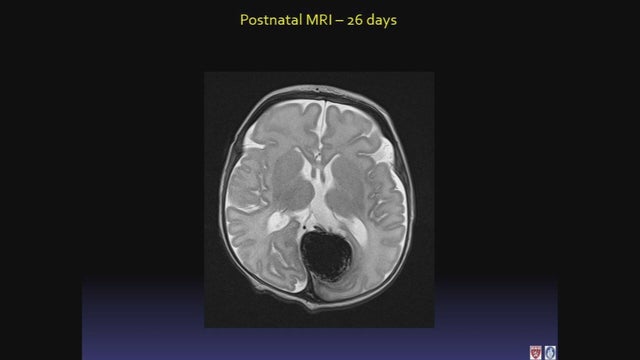

And this is the brain 26 days after the baby was born.